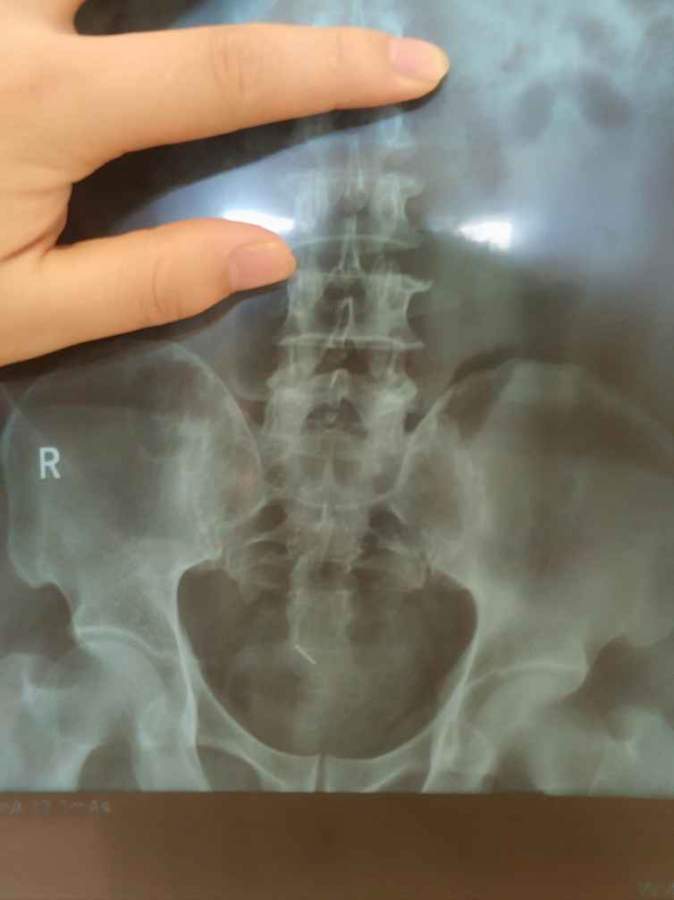

请问医学专业的师兄师姐,膀胱这里的亮钉子是啥 发自小木虫Android客户端 |